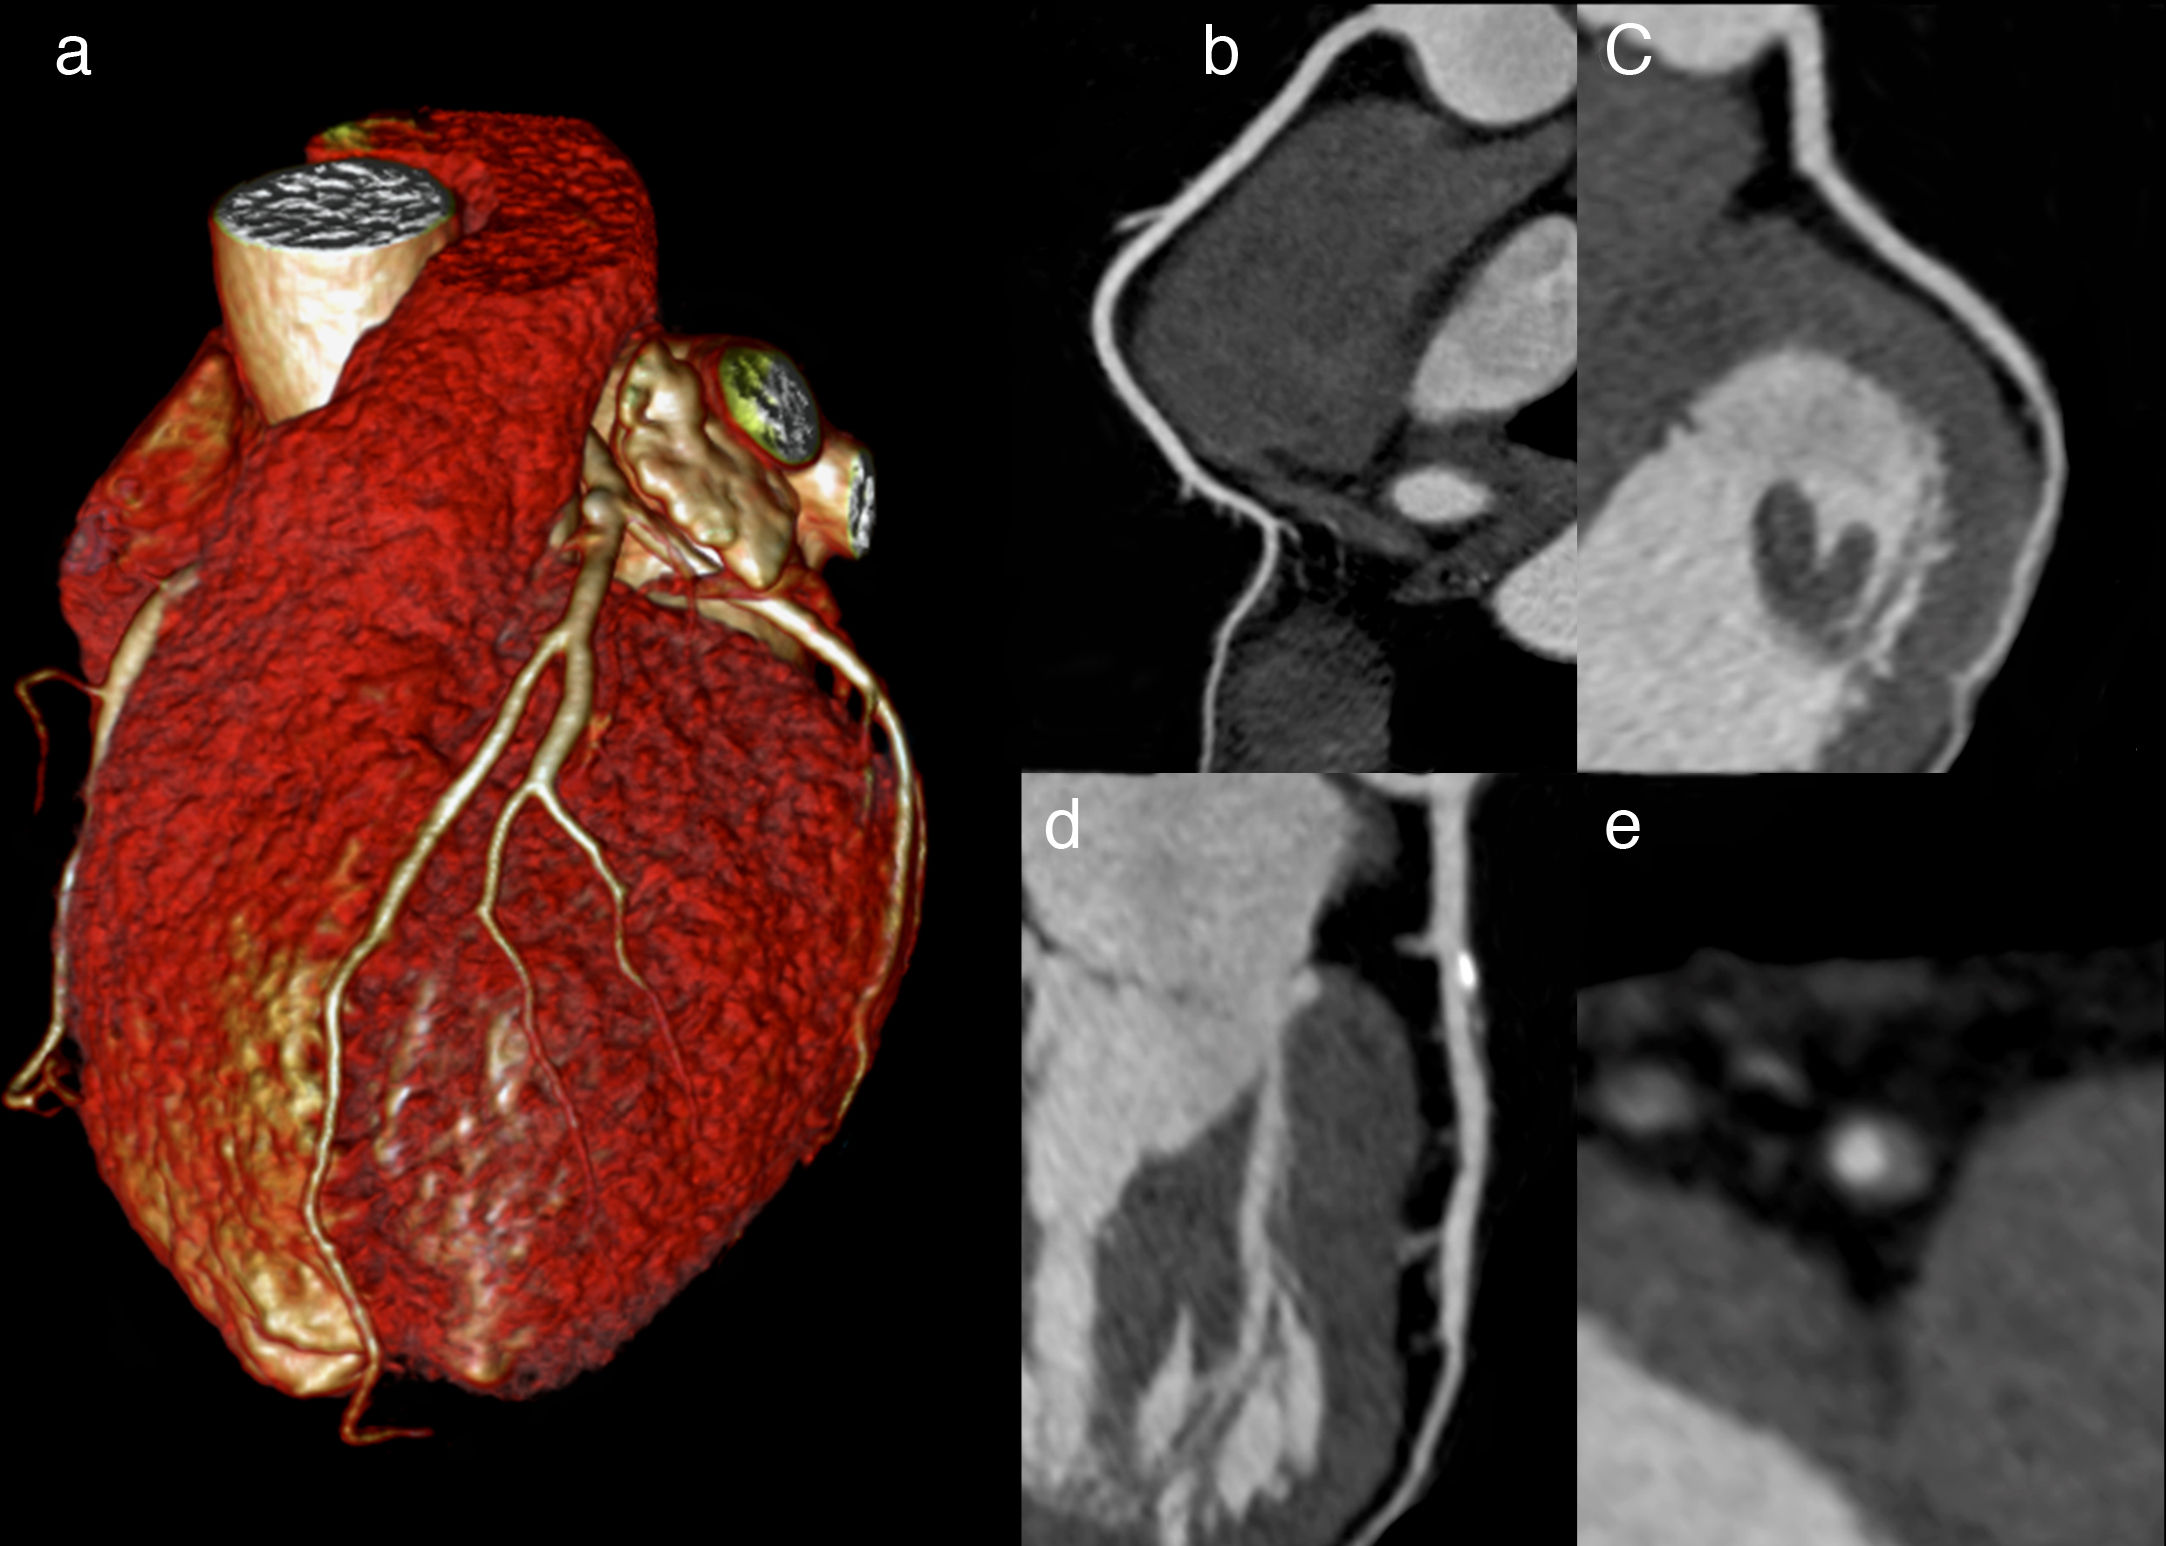

Coronariografía por tomografía computada vs Prueba de esfuerzo en el diagnóstico de enfermedad coronaria

03 octubre 2017

Ambas estrategias tuvieron similar mortalidad y necesidad de internaciones, si bien la tomografía computada mostró reducción de infartos de miocardio y aumento de procedimientos invasivos diagnósticos y terapéuticos. JAMA Internal Medicine, 2 de octubre de 2017